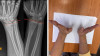

Ріст кістки зупинився після травми — утворився кістковий місток, який лікарі усунули малотравматичним методом.